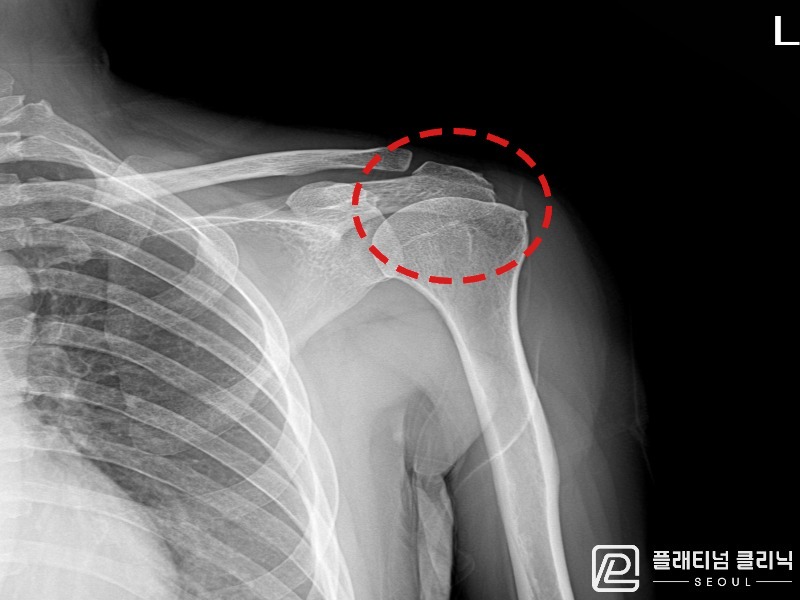

[촬영시기:21.09.27~21.10.07]

[석회분쇄흡입술] 우측 어깨의 야간 통증과 운동 제한으로 수개월간 고통받다 내원한 50세 남성 환자로, X-ray에서 극상근건 내 석회 침착이 확인되어 석회분쇄흡입술을 시행하였습니다.